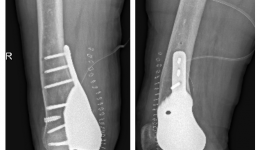

• 骨盆长出大恶瘤,“截”后重生创奇迹

骨盆长出大恶瘤,“截”后重生创奇迹

近日,我院骨与软组织肿瘤科成功救治一例盆骨巨大恶性肿瘤患者。患者整体恢复良好,并能在医护人员的指导下扶拐下地行走。55岁男性患者,因左臀部疼痛一年前来我院就诊。患者一年前无明显诱因出现左臀部疼痛,伴有包块发生,逐渐出现髋关节活动受限...